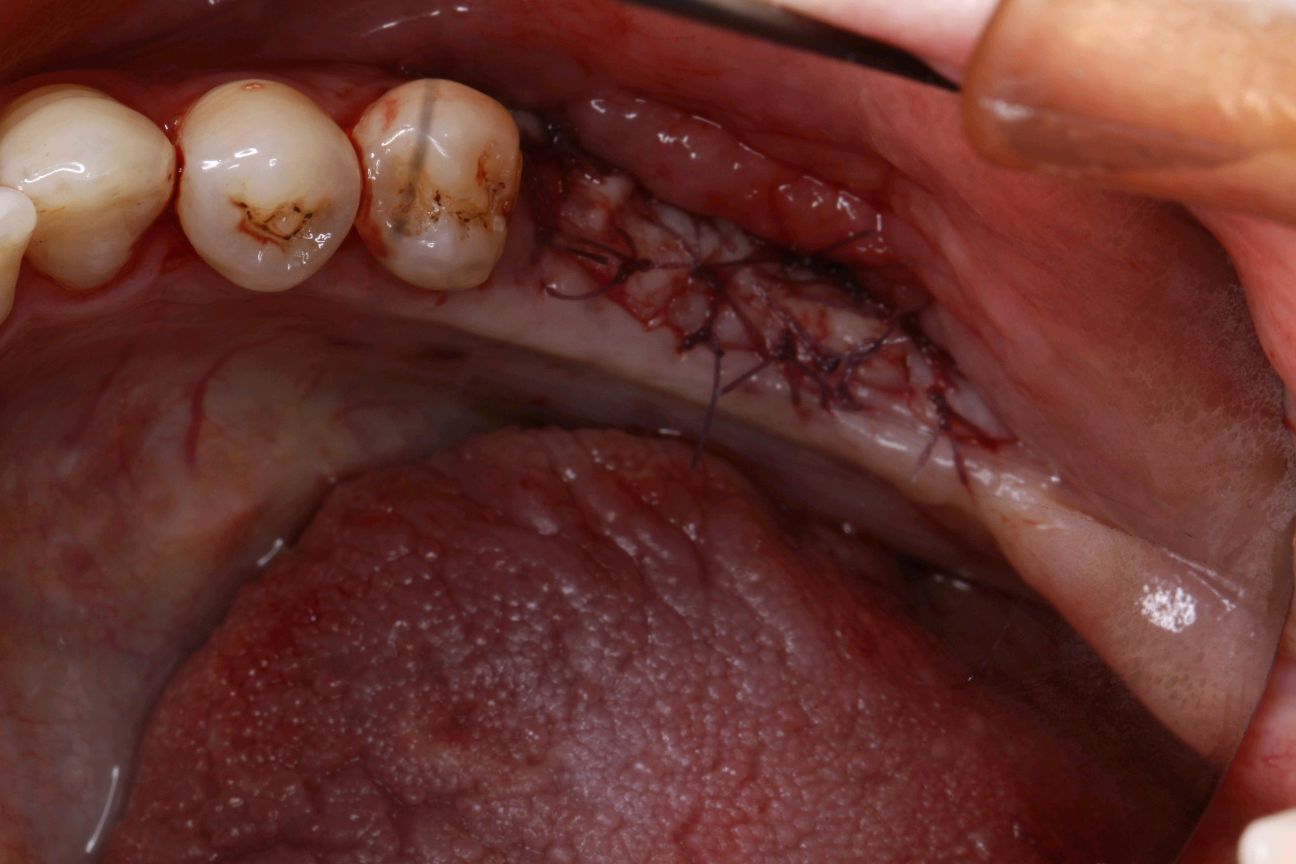

患者女30岁,左下后牙缺失已植入种植体,牙槽嵴呈刀刃壮,附着龈明显不足。角化牙龈缺乏易造成种植体抗炎屏障变弱,容易导致软组织炎症和边缘骨水平吸收。建议患者做游离牙龈移植术。通过获取自体健康游离龈瓣,移植到角化不足的患区,使种植体周围角化组织宽度增加,前庭沟加深。成功的话,会有良好的预后效果。